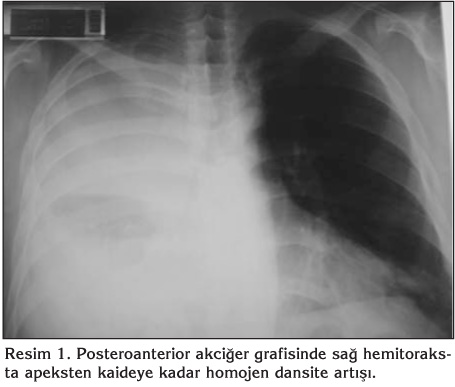

Klini?imize yat?r?ld???nda 39?C ate?, takipne (solunum say?s?: 28/dakika), perk?syonda sa? hemitoraksta matite ve osk?ltasyonda sa?da solunum sesi ?iddetinde azalma saptand?. Laboratuvar incelemesinde l?kosit 20.800/mm3, hemoglobin 12.3 g/dL, trombosit 433.000/mm3, sedimentasyon h?z? 100 mm/saat, aspartat aminotransferaz (AST) 52 U/L, alanin aminotransferaz (ALT) 54 U/L, oda havas?nda al?nan arteryel kan gaz?nda PaO2 51 mmHg bulundu. Posteroanterior akci?er grafisinde sa? hemitoraksta apeksten kaideye kadar homojen dansite art??? vard? (Resim 1). Pn?moni ve ampiyem tan?lar?yla antibiyotik tedavisi piperasilin-tazobaktam ile de?i?tirilirken olguya hemen bronkoskopi ve plevral ponksiyon yap?ld?. Endobron?iyal lezyon izlenmeyen olguda mikrobiyolojik de?erlendirmeler i?in ?rnekler al?nd?. Ultrasonografi (USG) e?li?inde yap?lan plevral ponksiyon sonucu 25 mL p?yden olu?an ?rnek al?nabildi. S?v?n?n biyokimyasal incelemesinde laktat dehidrogenaz (LDH) 29.300 U/L, total protein 5 g/dL, glukoz 10 mg/dL, adenozin deaminaz 76.3 U/L olarak saptan?rken, ?rne?in pH's?na teknik yetersizlikten dolay? bak?lamad?. Serbest plevral s?v? drene edilememesi nedeniyle ?ekilen toraks BT'de sa? hemitoraksta lok?lasyon g?steren masif plevral s?v?, plevral y?zeyde belirgin kal?nla?ma ve yayg?n mediastinal lenfadenopatiler g?r?ld? (Resim 2). G???s cerrahisi kons?ltasyonunda septik tablo nedeniyle cerrahi m?dahale d???n?lmedi. Sa? hemitoraksa vertebra ile skapula aras?na, toraks BT rehberli?inde ve USG e?li?inde ince plevral kateter (pl?rakan) tak?ld?. ?lerleyen g?nlerde toplam 1700 mL p?y bo?alt?ld?. Plevral s?v?n?n Gram boyamas?nda bakteri morfolojisi saptanmad? ve hasta ba??nda s?v?dan kan k?lt?r? besiyerine ekim yap?ld?. Al?nan bronkoskopik aspirasyon ve plevral s?v? ?rneklerinde bakteriyolojik, mikolojik, mikobakteriyolojik ?reme olmazken, patolojik inceleme sonucunda benign olarak de?erlendirildi. ?e?itli d?nemlerde al?nan kan ve balgam ?rneklerinde bakteriyolojik ?reme olmad?. Plevral kateter ile ilk bo?altma sonras? g?nde ortalama 200 mL plevral s?v? gelmeye devam eden olguda ???nc? g?nde, ate? kontrol alt?na al?nd?. Tedavinin yedinci g?n?nde tekrar ate?inde y?kselme ve l?kosit de?erlerinde d??me ba?lad?. Akci?er grafisinde d?zelme g?r?lmekle birlikte tekrarlanan toraks BT'de sa? hemitoraksta alt k?s?mda minimal lok?le s?v? oldu?u g?zlendi ve buradan USG e?li?inde ponksiyon denendi ama ?rnekleme yap?lamad?. Bu nedenle ?? g?n s?reyle mevcut plevral kateter yard?m? ile g?nl?k 250.000 ?nite intraplevral streptokinaz uygulanarak yap???kl?klar?n a??lmas? ve k???k lokalize alanlar?n drene olmas? planland? ancak minimum plevral s?v? d?n??? izlendi. Hemogram de?erleri giderek d??en olgunun l?kositi 1000/mm3 (n?trofil: %47, lenfosit: %49), hemoglobini 6.1 g/dL, trombositi 94.000/mm3, uluslararas? normalle?tirilmi? oran? (INR) 1.5 (0.91-1.09) ve aktive parsiyel tromboplastin zaman? (aPTT) 45.4 saniye (22.5-31.3) olarak saptand?. Hastaya eritrosit replasman? yap?ld?; antibiyotik tedavisi imipenem ve vankomisin ?eklinde tekrar d?zenlendi. Laboratuvar incelemelerinde AST 396 U/L, ALT 95 U/L, gamaglutamil transferaz (GGT) 127 U/L, LDH 4164 U/L, ferritin 5325 ng/mL (30-400), trigliserid 357 mg/dL (< 200) olarak saptand? (Tablo 1). Fizik muayenesinde v?cudunda yayg?n ?dem; g?vdesinde daha belirgin olmak ?zere t?m v?cutta ka??nt?l? mak?lopap?ler ve pete?iyal lezyonlar ile splenomegali geli?ti?i g?zlendi. ?nfeksiyonun tekrar alevlenmesi, laboratuvar de?erlerinin bozulmas?n?n nedeni olarak hastane k?kenli ya da farkl? etyolojide infeksiyon ve buna ba?l? sepsise gidi?, altta olas? hematolojik malignite ya da ba? dokusu hastal???nda atak d???n?ld?. Al?nan kan ve balgam ?rneklerinde ?reme saptanmad? ve serolojik testlerde; brusella, EBV, sitomegalovir?s (CMV), insan imm?nyetmezlik vir?s? (HIV), influenza, parainfluenza, respiratuar sinsityal vir?s (RSV) infeksiyonunu d???nd?recek bir bulgu g?zlenmedi (Tablo 2). Romatolojik belirte?leri normal saptanan olgunun kemik ili?i biyopsi ve aspirasyonu sonucu hipersel?ler kemik ili?i ve hemofagositoz; biyopside gran?lositer seride art??, aspirasyon preparat?nda gran?lositer seri hakimiyeti, %5 dolay?nda k???k lenfosit ve eritrosit fagositozu g?steren makrofaj saptand? (Resim 3, 4). Geli?en bu hemofagositoz sendromu tablosunun etyolojisi ve gen? sa?l?kl? bir ki?ide bu atipik infeksiyon seyrinin a??klamas? ?u ?ekilde yap?ld?; ilk a??r pn?moni ve ampiyem tablosuna sekonder geli?en hemofagositik sendrom, hastan?n imm?n direncini d???rerek hastane k?kenli infeksiyona yakalanmas?na neden olmu?tur. ?mipenem ve vankomisin tedavisi ile ate?i d??en, laboratuvar de?erleri d?zelen olguda; 21. g?nde tedavi sonland?r?ld?. Toplam 36 g?n hastanede kalan olgunun taburculu?undan bir ay sonraki kontrol?nde laboratuvar de?erleri normal olarak saptan?rken, akci?er grafisinde hafif d?zeyde plevral kal?nla?ma ve ?ekintiler d???nda patoloji g?zlenmedi.

Resim 2